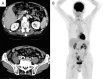

Protein-losing enteropathy (PLE) is a rare syndrome characterized by hypoproteinemia due to gastrointestinal (GI) protein loss. Primary intestinal follicular lymphoma (PIFL), a specific variant of follicular lymphoma with essential only GI involvement, has not been reported as an etiology of PLE. We herein report a case of PLE complicated with PIFL that was successfully treated with rituximab, resulting in rapid improvement of PLE and a complete response of PIFL. Macroscopic findings of ulcerative lesions with diffuse involvement, which were precisely described by capsule and double-balloon enteroscopy at the diagnosis, also improved following the treatment. This case provides a clue suggesting factors that promote PLE in PIFL.